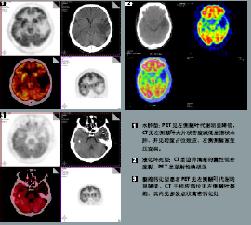

影像學表現:CT表現為斑片狀及斑點狀低密度影,MRI表現為點狀及片狀長T1WI長T2WI信號,由腦深部灰質團塊萎縮,胼胝體繼發變薄,致使腦室擴大,又由於瀰漫性髓鞘脫失而有不同程度的腦萎縮,顯示腦溝增寬,腦池擴大(如圖1~4)。有高血壓及動脈硬化的病理基礎也可發生腦出血是腔隙性梗塞的直接原因。

其它輔助檢查:1.腦電圖節律減慢至8~9Hz以下,雙側額區、顳區和中央區出現瀰漫性θ波可伴局灶性陣發高波幅δ節律視覺誘發電位(VEP)腦幹聽覺誘發電位(BAEP)和事件相關電位(ERP)P300的潛伏期均較同齡對照組明顯延長40%的患者不能誘發明顯的P300波形提示認知功能嚴重損害;2.影像學檢查CT可見腦皮質輕度萎縮,不同程度的腦室擴張,雙側腦室前角、后角及體部兩側出現邊界模糊的斑片狀低密度影可伴基底核、丘腦及腦橋等穿髓小動脈豐富區多發性腔隙性梗死。MRI檢查可見腦萎縮以白質為主,皮質較輕,雙側腦室周圍及半卵圓中心散在多發的T1WI低信號T2WI高信號伴多發腔隙性梗死灶PET檢查顯示雙側腦室周圍白質腦血流瀰漫性減少葡萄糖和氧代謝顯著降低。治療